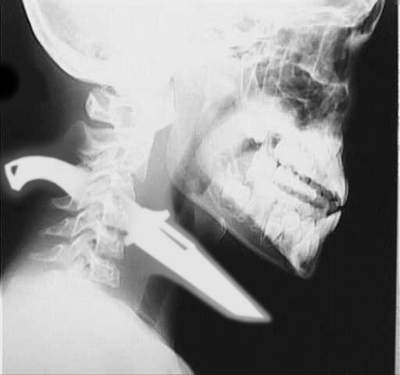

這張感覺超可怕的,好像是在店裡與人發生爭執~被對方用金屬製的椅子砸頭...最後也不知道怎麼搞的有一截就這樣活生生的從左眼窩刺穿到喉嚨...不過屌的是這個人好像沒死.............................................................